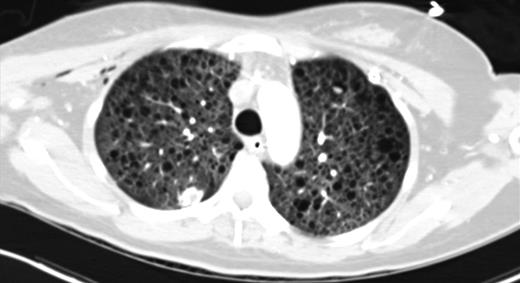

Upon admission, the patient's chest x-ray (CXR) was notable for bilateral interstitial infiltrates, and she was therefore started on empiric broad-spectrum antibiotics and oseltamivir. She was ventilated with lung-protective settings and paralyzed to alleviate ventilator dyssynchrony. Bronchoscopy revealed DAH and bronchioalveolar lavage cultures yielded Influenza A infection. She was started on high-dose methylprednisolone for her DAH, and inhaled nitric oxide (iNO) was added to optimize oxygenation. After a transient period of improvement, new infiltrates were appreciated on CXR, prompting computed tomography (CT) of her chest. This revealed multiple cysts throughout the lung parenchyma, suspicious for the diagnosis of LAM (Fig. 1).

CT chest (axial slices in lung window) demonstrating innumerable cysts scattered throughout all lung fields without basal/apical predilection or cardiophrenic sparing.